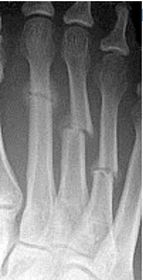

Describe the tubulation of the metatarsals | Metatarsals are overtubulated - decreased girth. |

Describe the tubulation of the metatarsals | Metatarsals are undertubulated - increased girth. |